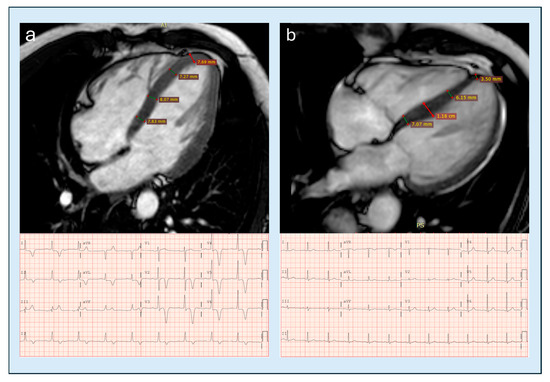

The use of non-invasive imaging techniques is undeniably one of the aspects that best characterize modern cardiology. With the implementation of percutaneous interventional procedures in the treatment of structural heart disease, and current advances in the management of chronic ischemic heart disease, metabolic storage diseases, and heart failure in clinical practice, imaging methods are required to provide increasingly sophisticated evaluation parameters, in order to adopt adequate therapeutic strategies and identify the patients best suited to undergo certain procedures. Therefore, clinicians in cardiac patient management cannot ignore the power of the complete and precise information provided by non-invasive diagnostic methods such as echocardiography, cardiac magnetic resonance imaging, cardiac CT, and nuclear cardiology, which can greatly facilitate correct diagnosis and adequate prognostic stratification.